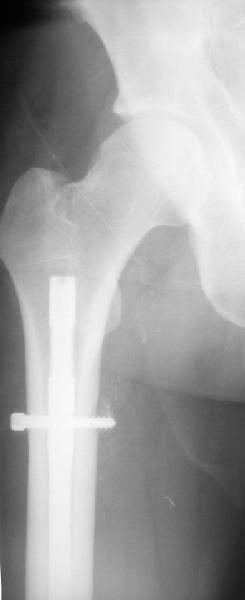

Удаление гвоздя ( гвоздь тонкий , поэтому похоже фиксация ротационно нестабильна)

В целом возражений нет, кроме как по предствленному снимку сложно судить о месте введения гвоздя, если через грушевидную ямку или в её районе, то все-таки риск повреждения медиальной огибающей артерии присутствует и кажется Джолдас приводил статистику о последующем развитии ав. некроза головки бедра при антеградном штифтовании через этот порт.

Если как на приложенной картинке - мало места?